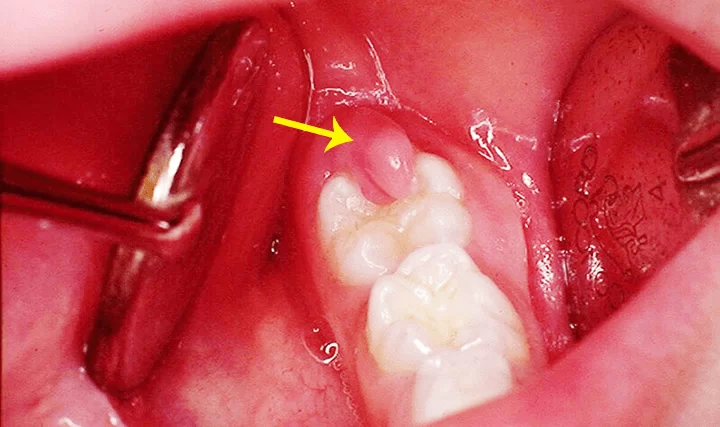

Răng số 8 có thể mọc ngược về phía xương hàm và đâm thưởng vào răng hàm lớn thứ hai hay còn gọi là răng số 7. Trong nhiều trường hợp, chúng có thể mọc theo hướng bình thường, nhú lên khỏi lợi một phần thì bị tắc và ngừng mọc vĩnh viễn. Điều này cũng có thể gây ra một số bệnh lý và ảnh hưởng đến sức khỏe răng miệng.

Trong những tình trạng răng khôn gây ra, mọc lệch chính là trường hợp phức tạp nhất, ảnh hưởng nhất đến răng miệng.

Răng khôn mọc lệch khiến chúng ta cảm thấy đau đớn

- Viêm lợi trùm răng khôn: tình trạng răng khôn mọc lệch thường đi kèm với tình trạng lợi trùm. Khi lợi bị trùm lên sẽ khiến thức ăn dễ bám lại ở lợi và răng, khó vệ sinh, tạo điều kiện để vi khuẩn sinh sôi gây ra nhiễm trùng.